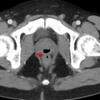

image Homem passa dois anos fazendo cocô pelo pênis e ejaculando pelo ânus; entenda o caso

As complicações podem ter sido causadas por um cateter que o paciente recebeu quando esteve em coma